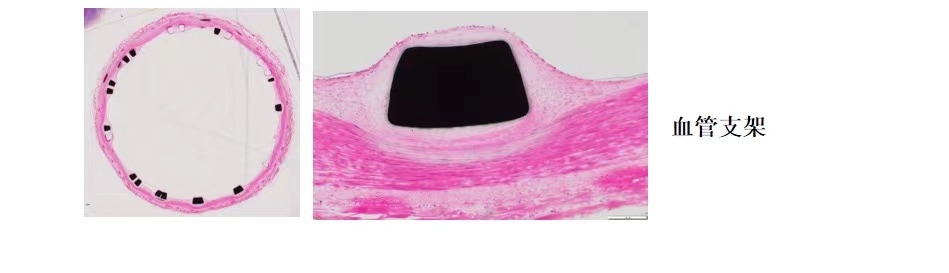

使用德国EXAKT切磨系统进行硬组织切片,特别是对于含有金属这类植入物的组织,是一种精确的组织切片技术。

各类尺寸的含金属植入物骨、牙齿、血管等硬组织样本脱水,7200树脂浸润包埋,后期用标准尺寸(25mm*75mm)的树脂片进行切磨片处理。

将包埋好的硬组织树脂块,用EXAKT 硬组织切片机先切一个200um的厚片,然后再通过EXAKT 硬组织磨片机将其磨到20-30um薄片,样本是已经硬组织包埋好的含金属的动物样本。

具体步骤:包埋块修开切面抛光-平行粘片装置粘片-硬组织切片机切片-硬组织磨片机磨片抛光成片。

针对不同的病理阅片指标需求,行HE染色、Masson染色、亚甲基蓝-酸性品红染色、VG染色、Movat染色等。